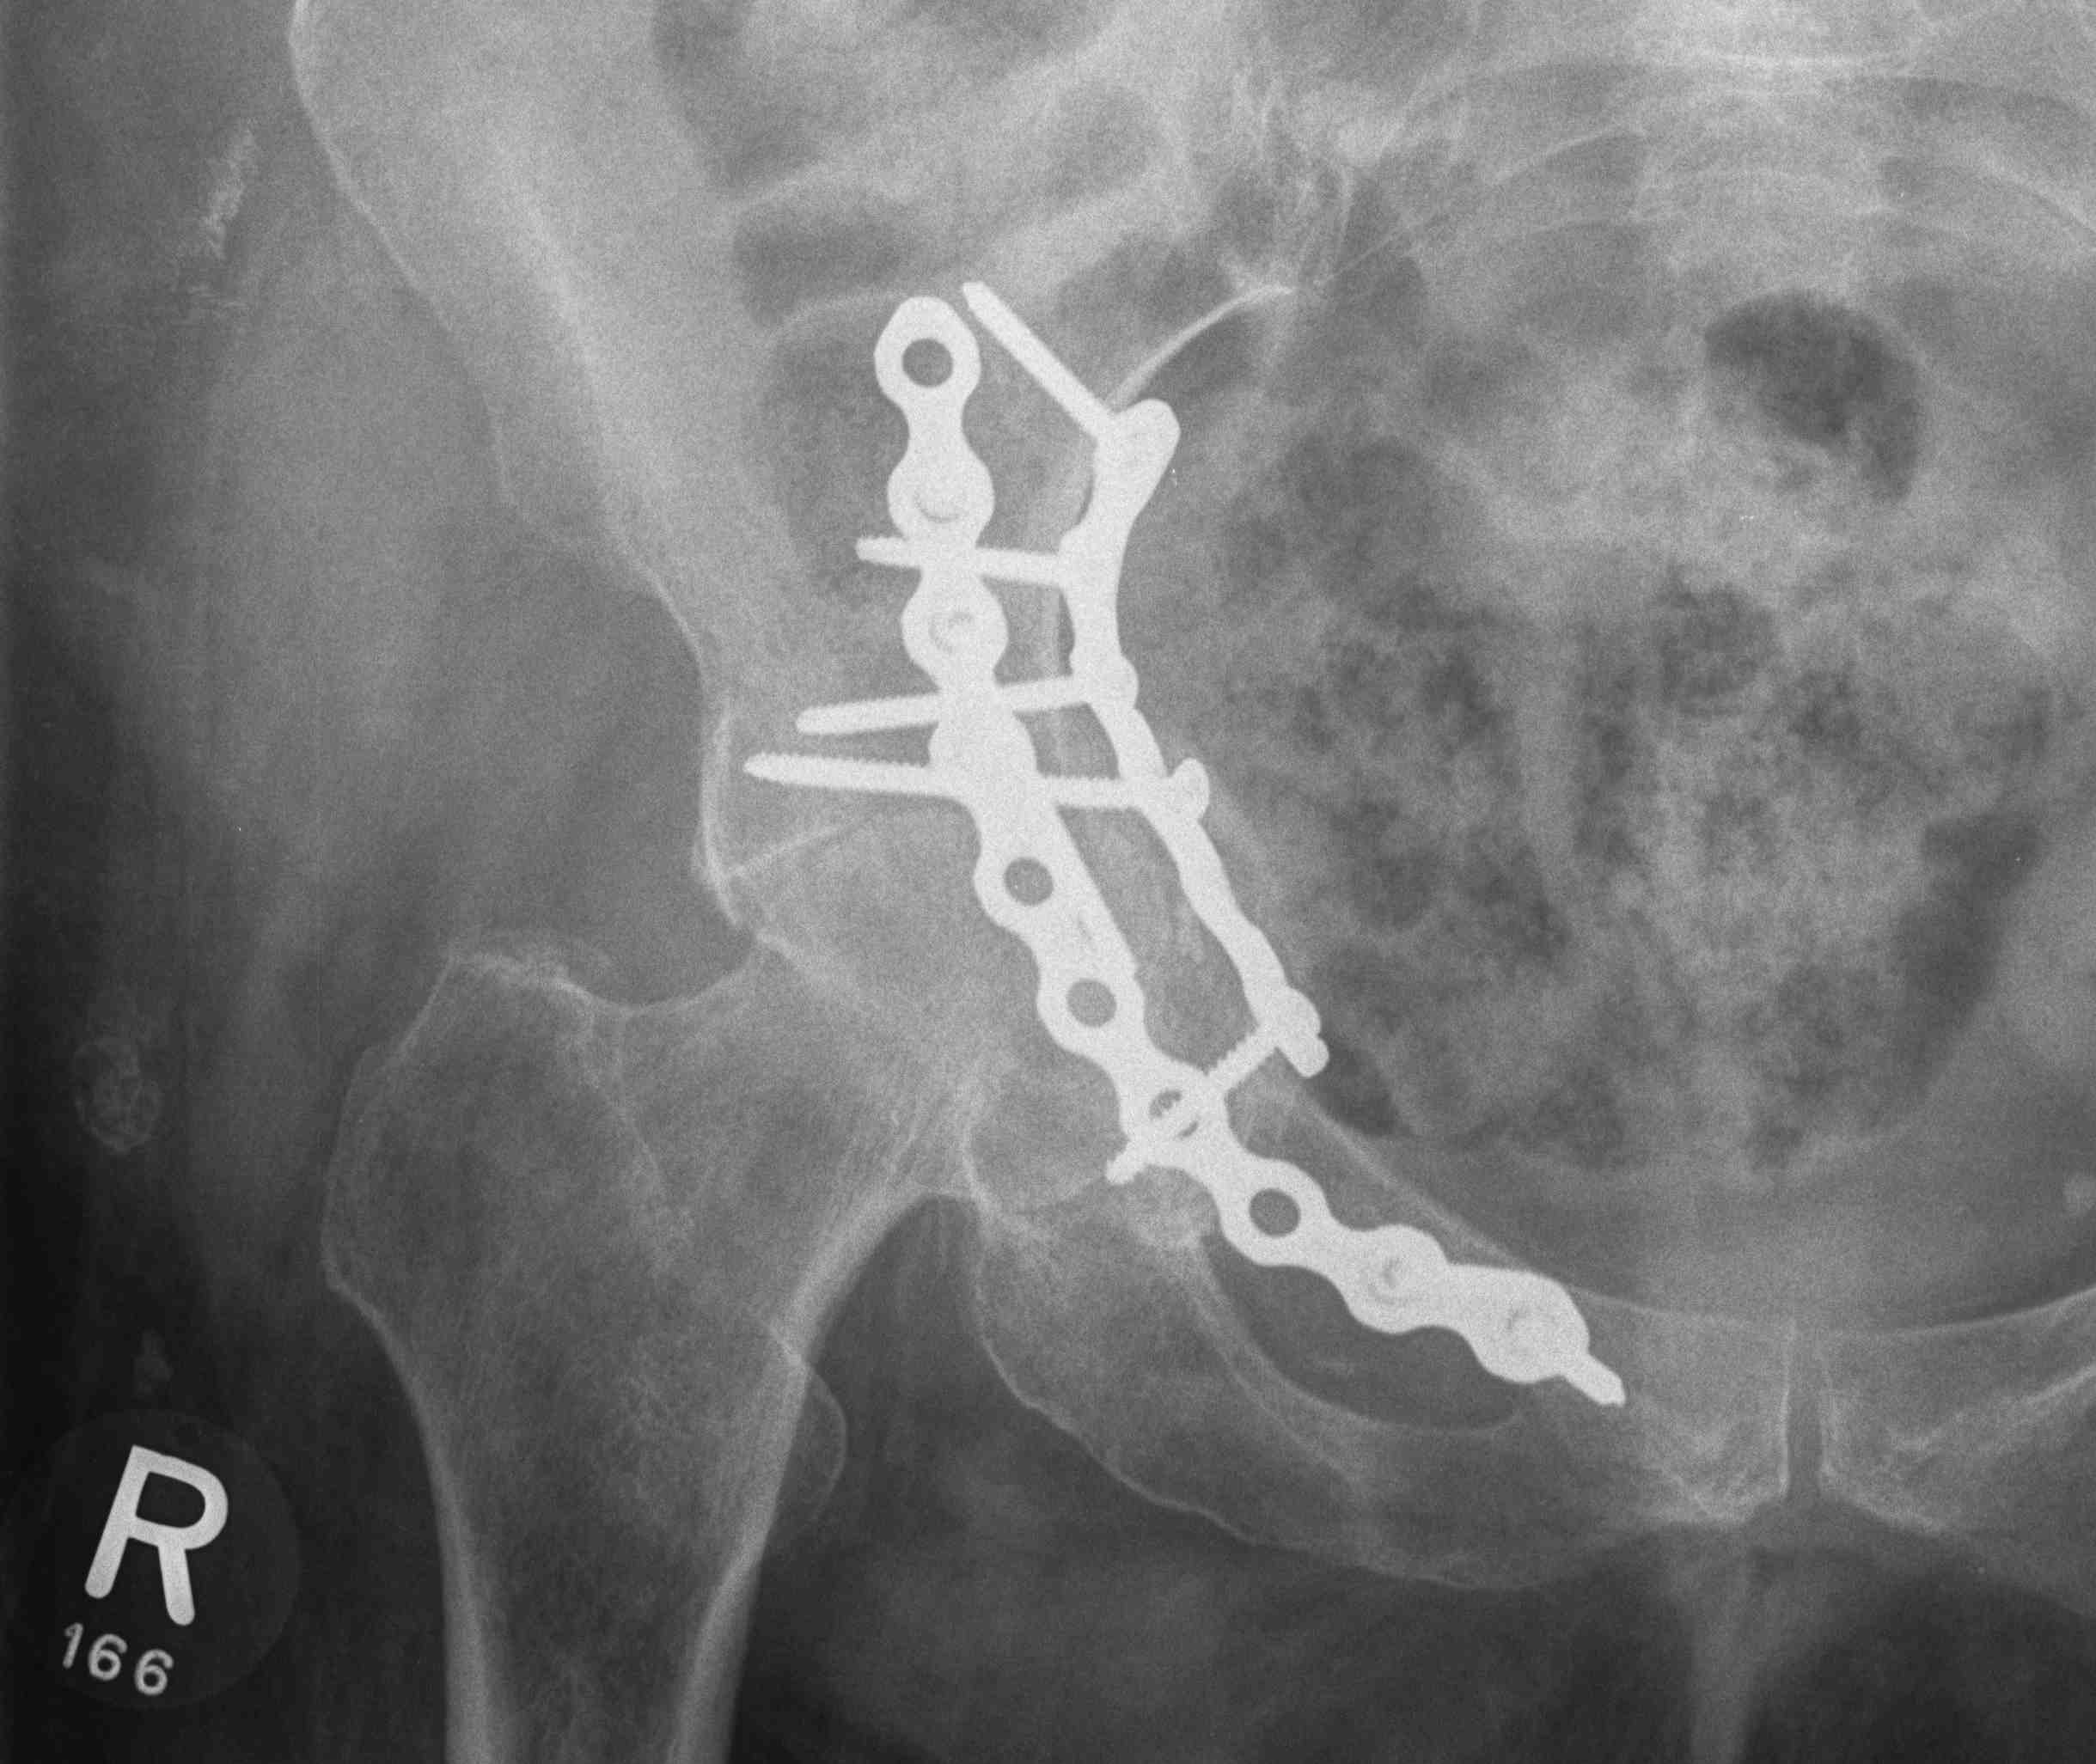

ORIF

Aim

1. Anatomic reduction

2. Provisional fixation with lag screws

3. Buttressing with curved reconstruction plates

Options

1. Posterior / Kocher-Langenbeck approach

- posterior column / wall

2. Ilioinguinal approach

- anterior column / wall